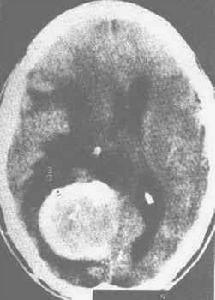

CT圖在CT出現以前,根據病人的臨床表現,再輔以頭顱平片和腦血管造影,對腦膜瘤即可作出確診。CT的出現,使眶腦膜瘤的定位以及定性診斷水平大大提高,典型的眶腦膜瘤,在未增強的CT掃描中,呈現孤立的等密度或高密度占位病變,其密度均勻一致,邊緣清晰瘤內可見鈣化。

CT平掃圖並發疾病